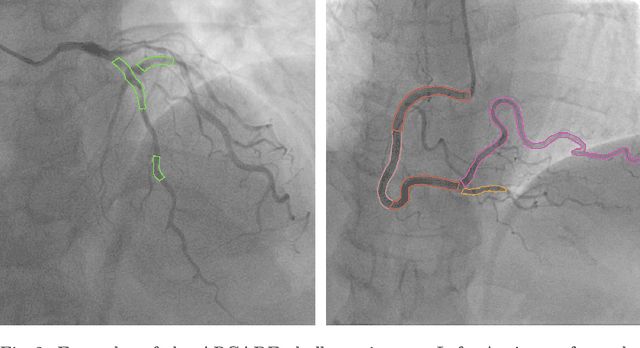

Abstract:Coronary artery stenosis is a critical health risk, and its precise identification in Coronary Angiography (CAG) can significantly aid medical practitioners in accurately evaluating the severity of a patient's condition. The complexity of coronary artery structures combined with the inherent noise in X-ray images poses a considerable challenge to this task. To tackle these obstacles, we introduce a semi-supervised approach for cardiovascular stenosis segmentation. Our strategy begins with data augmentation, specifically tailored to replicate the structural characteristics of coronary arteries. We then apply a pseudo-label-based semi-supervised learning technique that leverages the data generated through our augmentation process. Impressively, our approach demonstrated an exceptional performance in the Automatic Region-based Coronary Artery Disease diagnostics using x-ray angiography imagEs (ARCADE) Stenosis Detection Algorithm challenge by utilizing a single model instead of relying on an ensemble of multiple models. This success emphasizes our method's capability and efficiency in providing an automated solution for accurately assessing stenosis severity from medical imaging data.

Abstract:Accurate segmentation of coronary arteries is a pivotal process in assessing cardiovascular diseases. However, the intricate structure of the cardiovascular system presents significant challenges for automatic segmentation, especially when utilizing methodologies like the SYNTAX Score, which relies extensively on detailed structural information for precise risk stratification. To address these difficulties and cater to this need, we present MPSeg, an innovative multi-phase strategy designed for coronary artery segmentation. Our approach specifically accommodates these structural complexities and adheres to the principles of the SYNTAX Score. Initially, our method segregates vessels into two categories based on their unique morphological characteristics: Left Coronary Artery (LCA) and Right Coronary Artery (RCA). Specialized ensemble models are then deployed for each category to execute the challenging segmentation task. Due to LCA's higher complexity over RCA, a refinement model is utilized to scrutinize and correct initial class predictions on segmented areas. Notably, our approach demonstrated exceptional effectiveness when evaluated in the Automatic Region-based Coronary Artery Disease diagnostics using x-ray angiography imagEs (ARCADE) Segmentation Detection Algorithm challenge at MICCAI 2023.